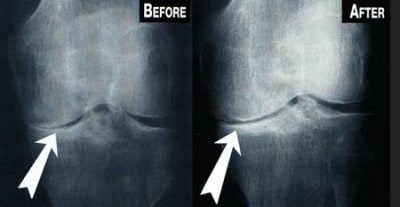

Before After Stem Cell Therapy for Arthritis